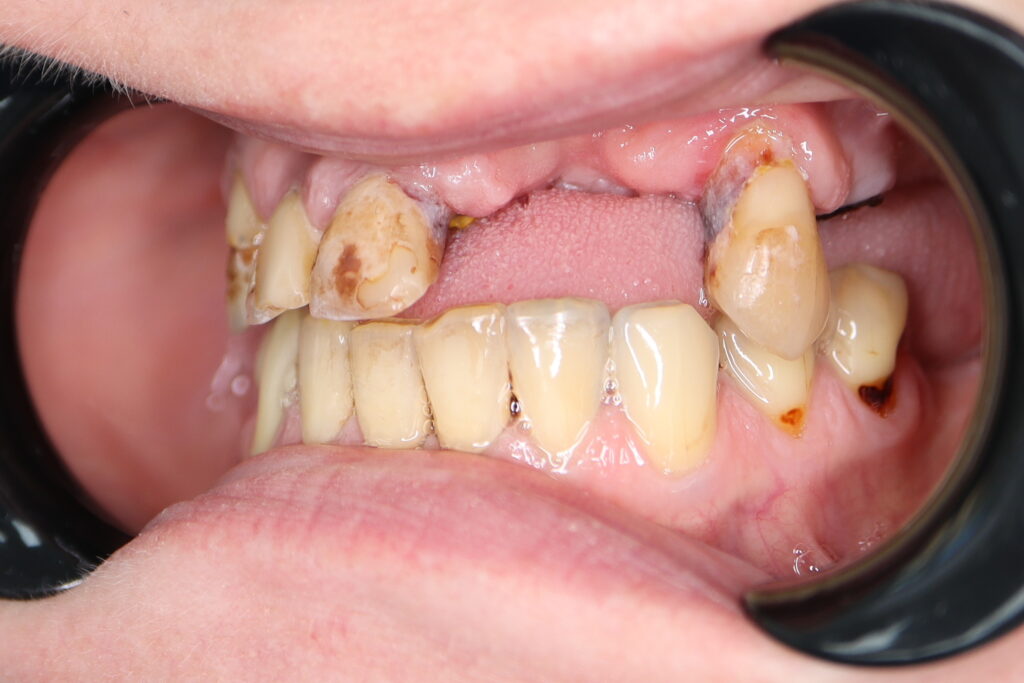

Процесс работы

Что было сделано:

На верхней челюсти были удалены зубы, которые находились в неудовлетворительном состоянии. Удалена киста в области зуба 2.1.

Установлены 5 имплантантов Megagen Anyone и сняты оттиски.

Спустя 5 дней на верхней челюсти зафиксирован протез из пластмассы, армированный металлической балкой из КХС (кобальт-хромовый сплав) с опорой на 5 дентальных имплантатов.